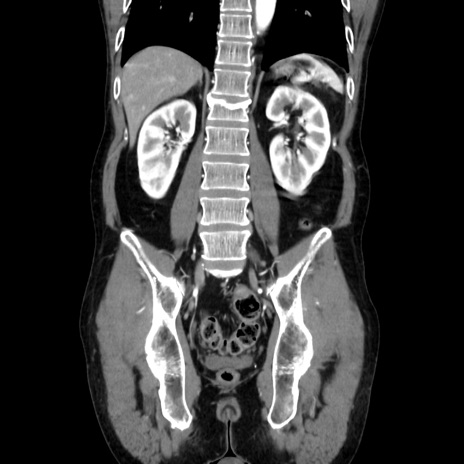

症例37(冠状断像)

横断像

【症例】40歳代 男性

【主訴】腹痛

【現病歴】4時間ほど前に電車に乗車中に臍部上より腹痛出現。徐々に増悪し起立困難となり、救急外来受診。生ものは数日食べていない。今朝お雑煮を食べた。

【既往歴】なし

【身体所見】BT 36.8℃、BP 117/84mmHg、HR 91/min、SpO2 97%、苦悶様、腹部:臍上部広範囲圧痛あり、反跳痛±

【データ】WBC 8100、CRP 0.03